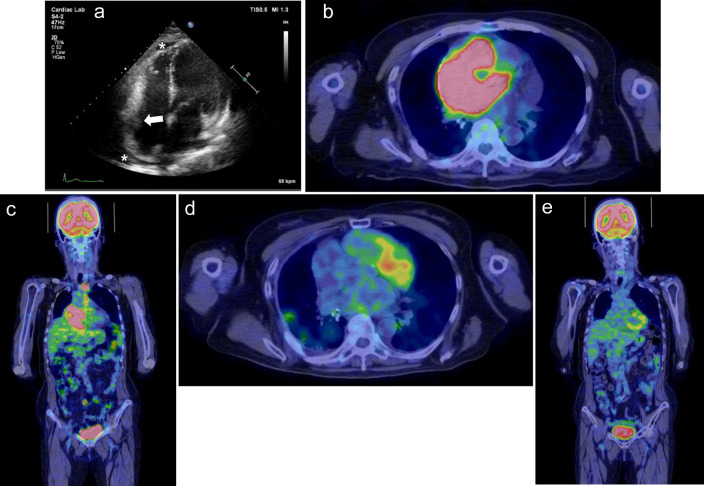

Primary cardiac lymphoma is a rare, often fatal malignancy that can cause disorders of conduction depending on tumor location. We report two cases with sick sinus syndrome and atrial flutter secondary to primary cardiac lymphoma originating from the right atrium. One case required pacemaker implantation in the chronic phase after complete remission of lymphoma, and the other case in the acute phase when cardiac mass occupied the right atrium. Depending on the disease activity of lymphoma including its size, growth rate, and degree of invasion, the clinical course of sinus node dysfunction varies between each patient. In patients with conduction disorders, we suggest that long-term cardiac monitoring is necessary not only at onset but also after complete remission of lymphoma.